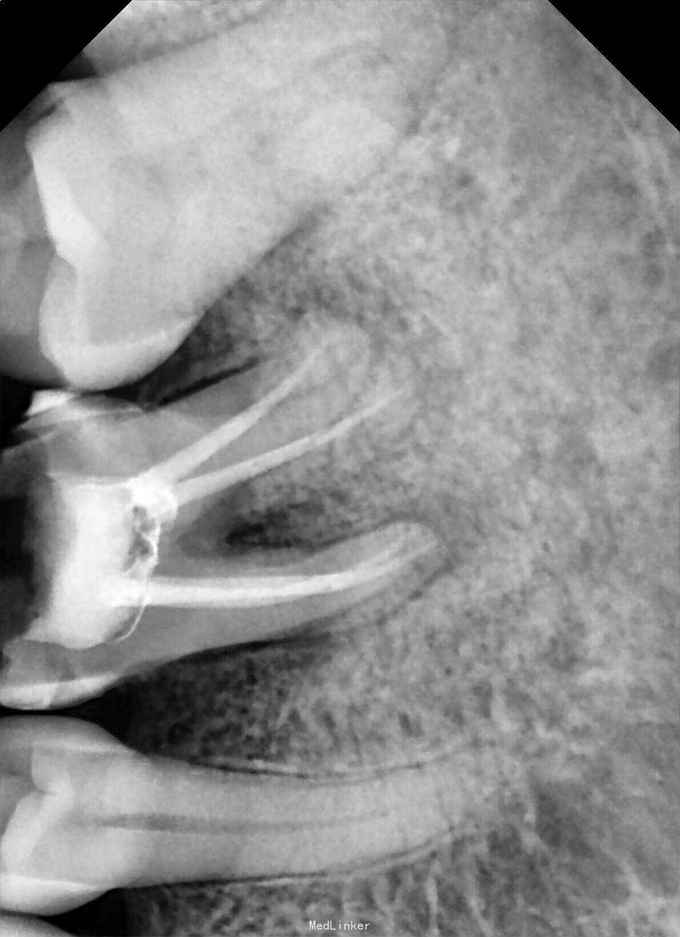

检查:36牙残冠,开髓洞型,叩(+),松(-) 辅查:36牙远中根管口有异物,根尖暗影

诊断:36牙慢性根尖周炎 治疗:36牙探及根管口④,远颊根管口阻塞,选用尖头金刚砂车针去除部分髓底,暴露断针头部,超声(P尖)逆时针振荡,直到断针松动,然后用血管钳取出断针,疏通根管,机扩,充填,术后1个月复查,根尖暗影范围略有缩小